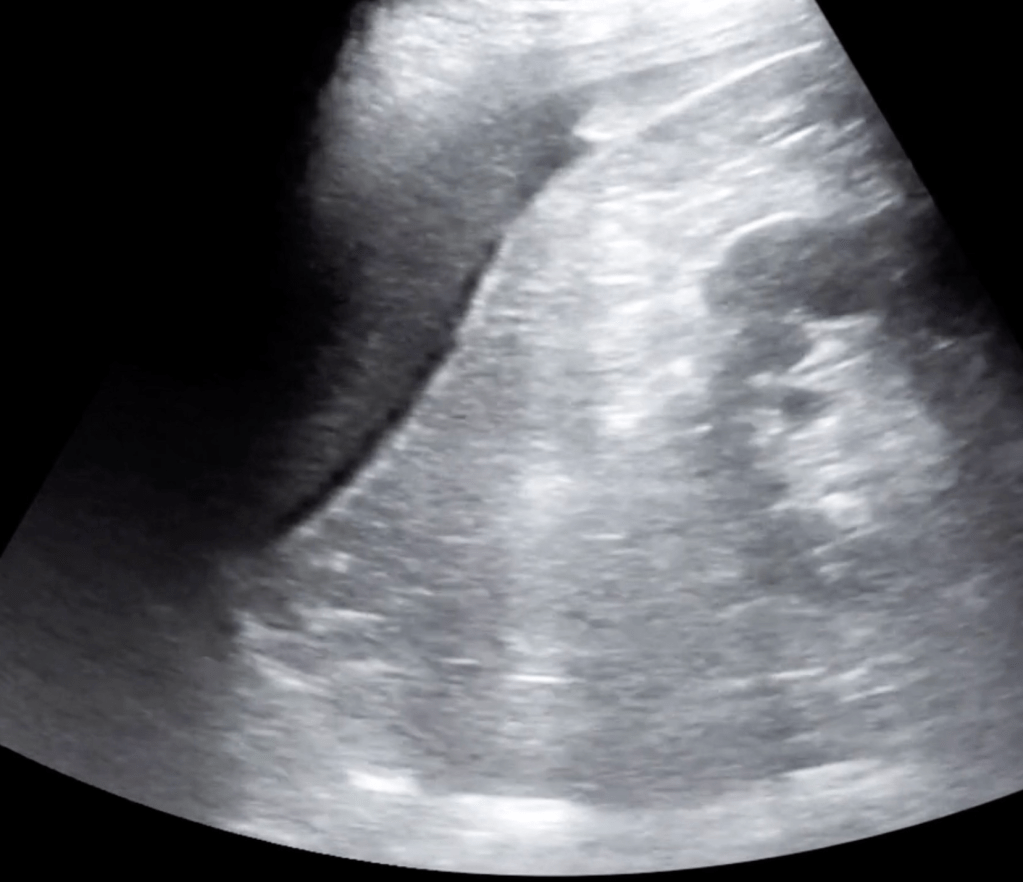

5 Minute Sono

- Large curvilinear probe

- Graded compression up and down

- Diverticula

- Bowel wall>5mm

- Prominent fluid-filled bowel loops

- Pericolic free fluid

- Increased pericolic fat (hyperechoic)

- Abscess